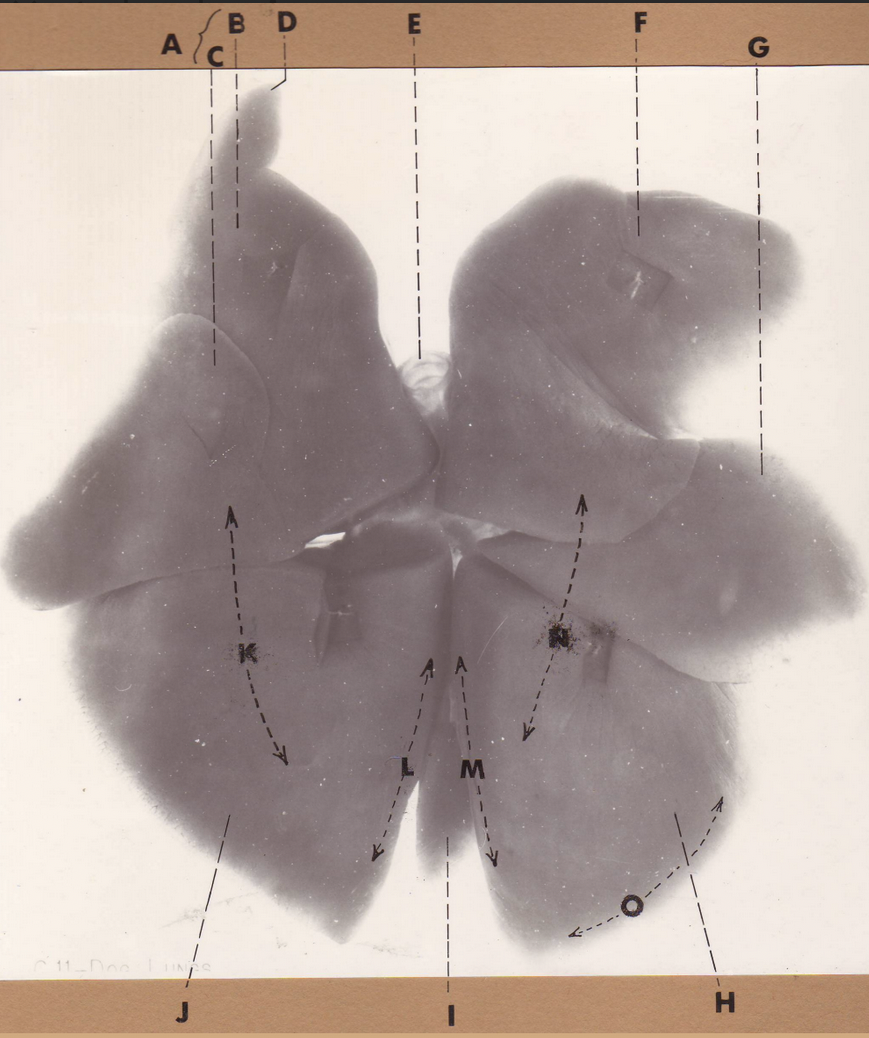

A

(cat larynx/trachea/lungs, dorsal)

epiglottis

B

(cat larynx/trachea/lungs, dorsal)

larynx

C

(cat larynx/trachea/lungs, dorsal)

trachea

D

(cat larynx/trachea/lungs, dorsal)

R cranial lobe

E

(cat larynx/trachea/lungs, dorsal)

middle lobe

F

(cat larynx/trachea/lungs, dorsal)

R caudal lobe

G

(cat larynx/trachea/lungs, dorsal)

primary bronchi

H

(cat larynx/trachea/lungs, dorsal)

L caudal lobe

I

(cat larynx/trachea/lungs, dorsal)

L cranial lobe

J

(cat larynx/trachea/lungs, dorsal)

cricoarytenoideus dorsalis m

K

(cat larynx/trachea/lungs, dorsal)

thyroid

A

(cat larynx/trachea/lungs, dorsal)

epiglottis

B

(cat larynx/trachea/lungs, dorsal)

larynx

C

(cat larynx/trachea/lungs, dorsal)

trachea

D

(cat larynx/trachea/lungs, dorsal)

R cranial lobe

E

(cat larynx/trachea/lungs, dorsal)

middle lobe

F

(cat larynx/trachea/lungs, dorsal)

R caudal lobe

G

(cat larynx/trachea/lungs, dorsal)

primary bronchi

H

(cat larynx/trachea/lungs, dorsal)

L caudal lobe

I

(cat larynx/trachea/lungs, dorsal)

L cranial lobe

J

(cat larynx/trachea/lungs, dorsal)

cricoarytenoideus dorsalis m

K

(cat larynx/trachea/lungs, dorsal)

thyroid